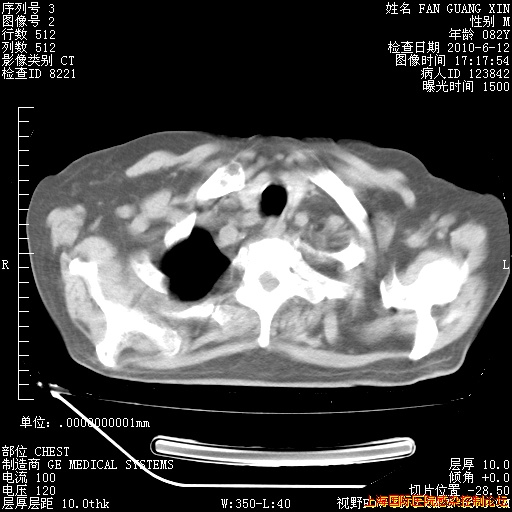

补发6月12日肺部CT肺窗

6月12日肺窗